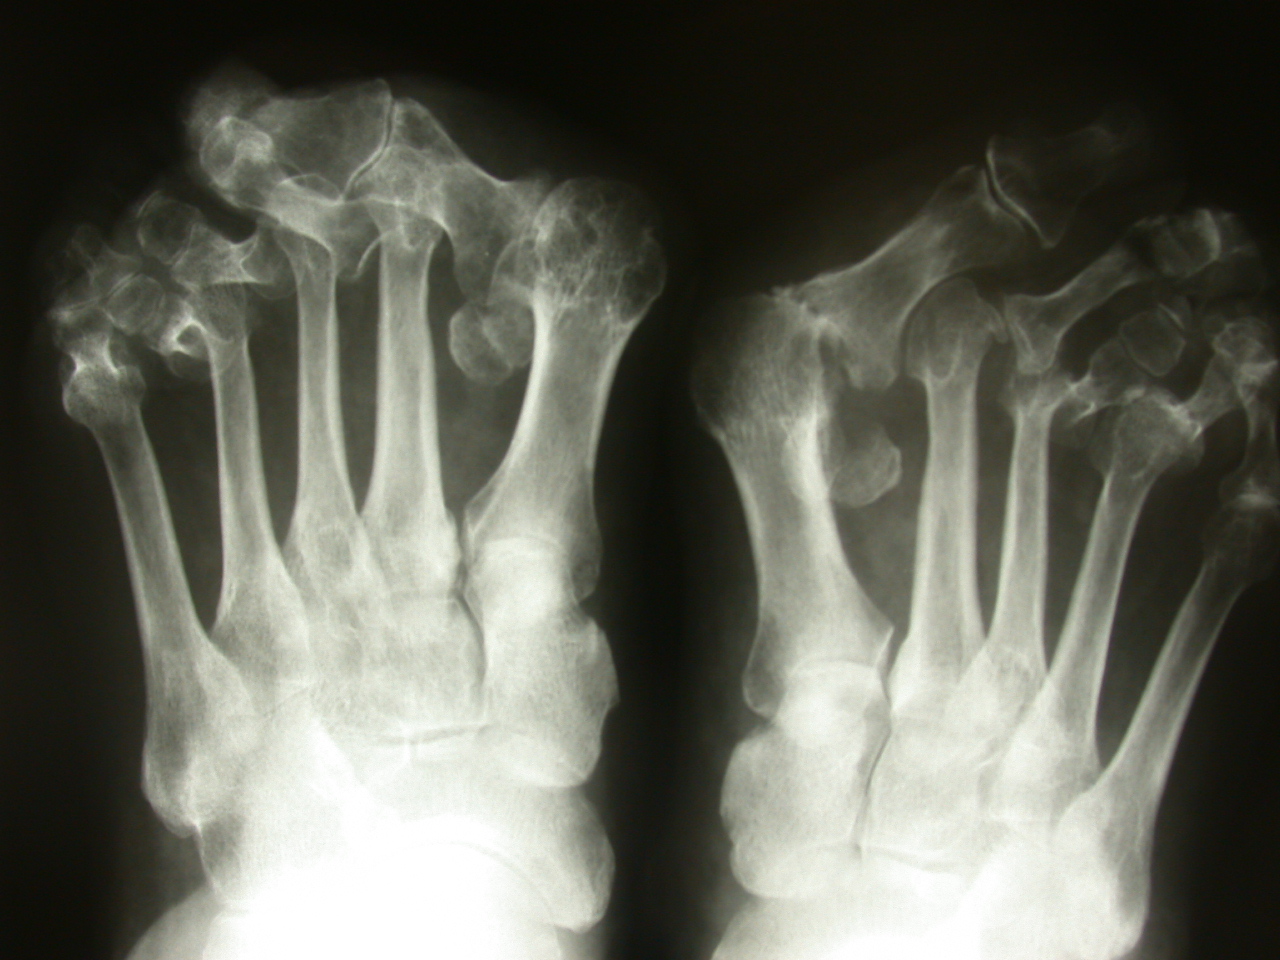

• sull’esame radiografico (riduzione dello spazio articolare , rarefazione ossea , in fase avanzata erosioni dei capi articolari e sublussazioni o vere e proprie lussazioni patologiche)

Tipicamente l’esordio è caratterizzato da dolori articolari accompagnati da tumefazione e rigidità che interessano le articolazioni di mani e piedi in maniera simmetrica ed aggiuntiva (cioè interessamento di altre articolazioni senza regressione nelle sedi già colpite). A livello del piede le articolazioni più frequentemente interessate sono le metatarso-falangee cioè le articolazioni alla base delle dita che vanno spesso incontro a lussazione patologica ; con minor frequenza sono interessate le articolazioni del retropiede e della caviglia (tra astragalo e scafoide , tra astragalo e calcagno, tibiotarsica). Se non adeguatamente trattata compaiono ipertrofia sinoviale ed erosioni dei capi articolari che comportano caratteristiche deformità ; in particolare all’avampiede si realizza spesso deformità in valgismo (cioè verso l’esterno) dell’alluce e delle dita laterali. Al retropiede il problema più comune è la comparsa di un progressivo piattismo che può arrivare a situazioni molto gravi per instabilità delle articolazioni interessati e per progressivo cedimento delle strutture tendinee , in particolare del tibiale posteriore.